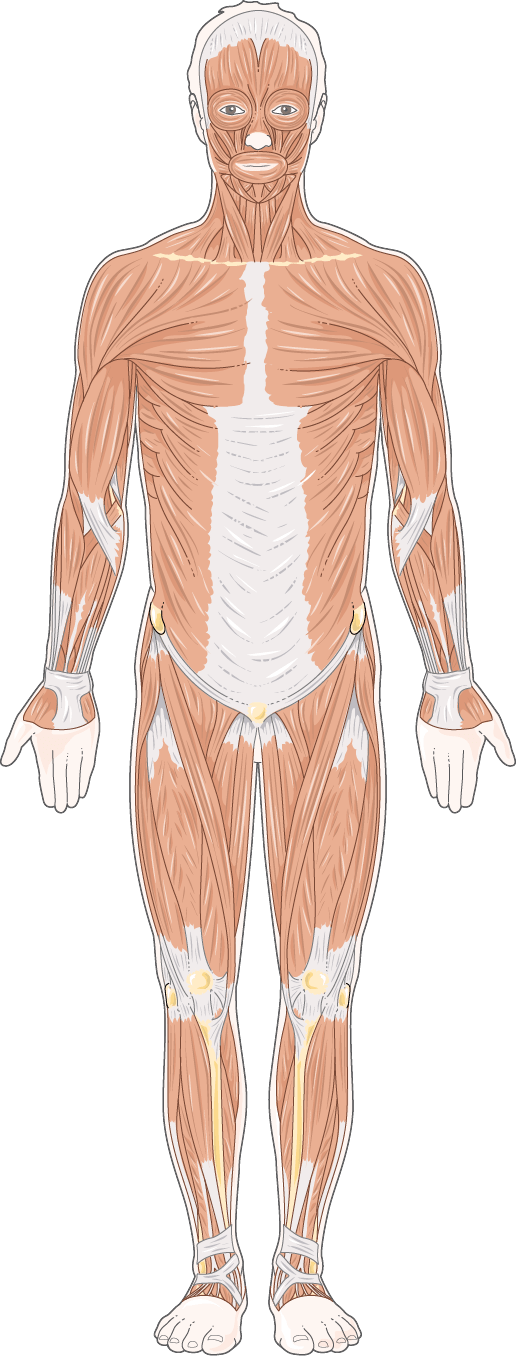

Lo más inmediato es empezar por practicar un montón la anatomía humana (a menos que lo tuyo sea la veterinaria, para lo cual también tendrías que checar libros pertinentes acerca del tema).

Si empiezas desde el trasfondo del artista, probablemente lo más recomendable sea checar libros de anatomía artística más especializados y de ahí escalar hacia publicaciones de corte mucho más médico, pues es ahí donde el dibujar ilustración médica entra en verdadero detalle acerca de todo tipo de sistemas, órganos y demás elementos de carácter biológico mucho más específicos.

“Más específicamente, un ilustrador médico crea obras artísticas que resultan tanto visualmente agradables como médica y científicamente correctas. Como Ilustradora médica, puedo crear una variedad de trabajos artísticos que incluyen ilustraciones médicas y científicas, diseños de interfaces multimedia, animaciones en 2 y 3 dimensiones, así como también storyboards para profesionales médicos y de la salud, investigadores, agencias de publicidad, compañías farmacéuticas, abogados de lesiones personales, y para el público en general.”

En la ilustración médica, lo primero que podemos notar es que los dibujos nos ayudan a capturar con precisión ciertas partes u órganos en los que queremos enfatizar, pudiendo incluso aumentar el nivel de detalle para visualizarlos cuanto queramos además de poder ubicarlos en diferentes perspectivas dentro del espacio que ocupan originalmente en nuestro cuerpo, ya sea en 2D o 3D, sin todas las complicaciones que esto significaría al tomar una fotografía.